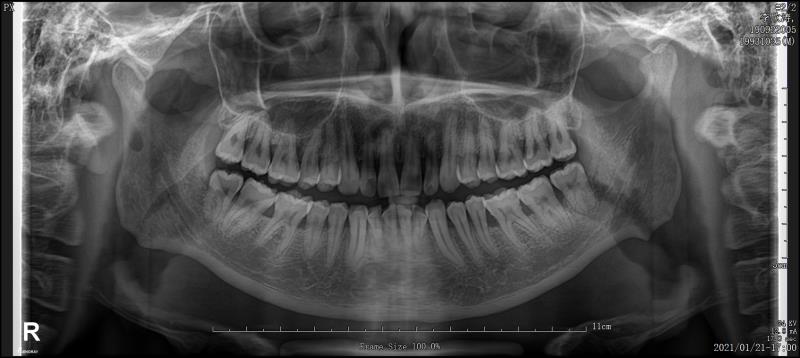

- 首先要找靠谱的医生去面诊,详细了解一下自己 的情况,面诊检查【拍片、照相、取牙模】 后面有详细介绍

PS: 前期准备工作包括(全景片 ,头颅侧位片 ,CT ,6张口内 照片,6张面相照 , 模型,补牙,洁牙…)